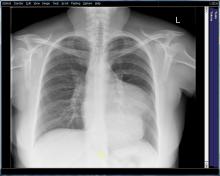

Figure 1: PA Chest radiograph revealing a soft tissue density measuring 6.7 x 9 cm, merging with the left heart border. Most likely vascular in origin, however mediastinal masses could not be ruled out.

The patient’s neurological symptoms continued to improve with only minor residual weakness in her left arm. She began to demonstrate signs of progressive cardiac failure. Subsequent serial TTE demonstrated a progressively enlarging inferior aneurysm. Coronary angiography showed her to have an occluded right coronary artery. Chest radiography and CT scan of the thorax showed a very large aneurysmal dilatation of the left ventricle containing a moderate amount of thrombus (Figure 1 [3]). The aneurysm arose from the inferior wall of the mid cavity of the ventricle. Its neck measured approximately 40 mm. The aneurysm itself measured 110 x 90 x 120 mm. The left ventricle was dilated with thinning of the myocardium globally. In contrast, the cardiac MRI (Video 1,2) showed that the left ventricle had a ruptured inferior free wall measuring 30 x 32 mm, which opened into an inferior pseudoaneurysm measuring 60 mm deep and 99 mm across, with a significant layer of thrombus.